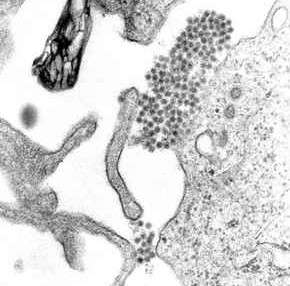

Mosquitoes thrive in the high temperatures and humidity of the Bolivian lowlands and it was that region which saw the highest numbers of infected civilians.[1] There is currently no vaccine for dengue fever.[1] Those infected experience flu-like symptoms such as severe headaches, fevers and joint pain.[1] The infected are advised by medical experts to drink lots of fluids and obtain significant rest.[1] Dengue fever sufferers have an approximate 1% chance of progressing to the more severe dengue hemorrhagic fever.[1] Symptoms for such a progression include hypothermia, vomiting, severe abdominal pain and confusion. The global average case-fatality ratio for dengue hemorrhagic fever is 5%.[1]